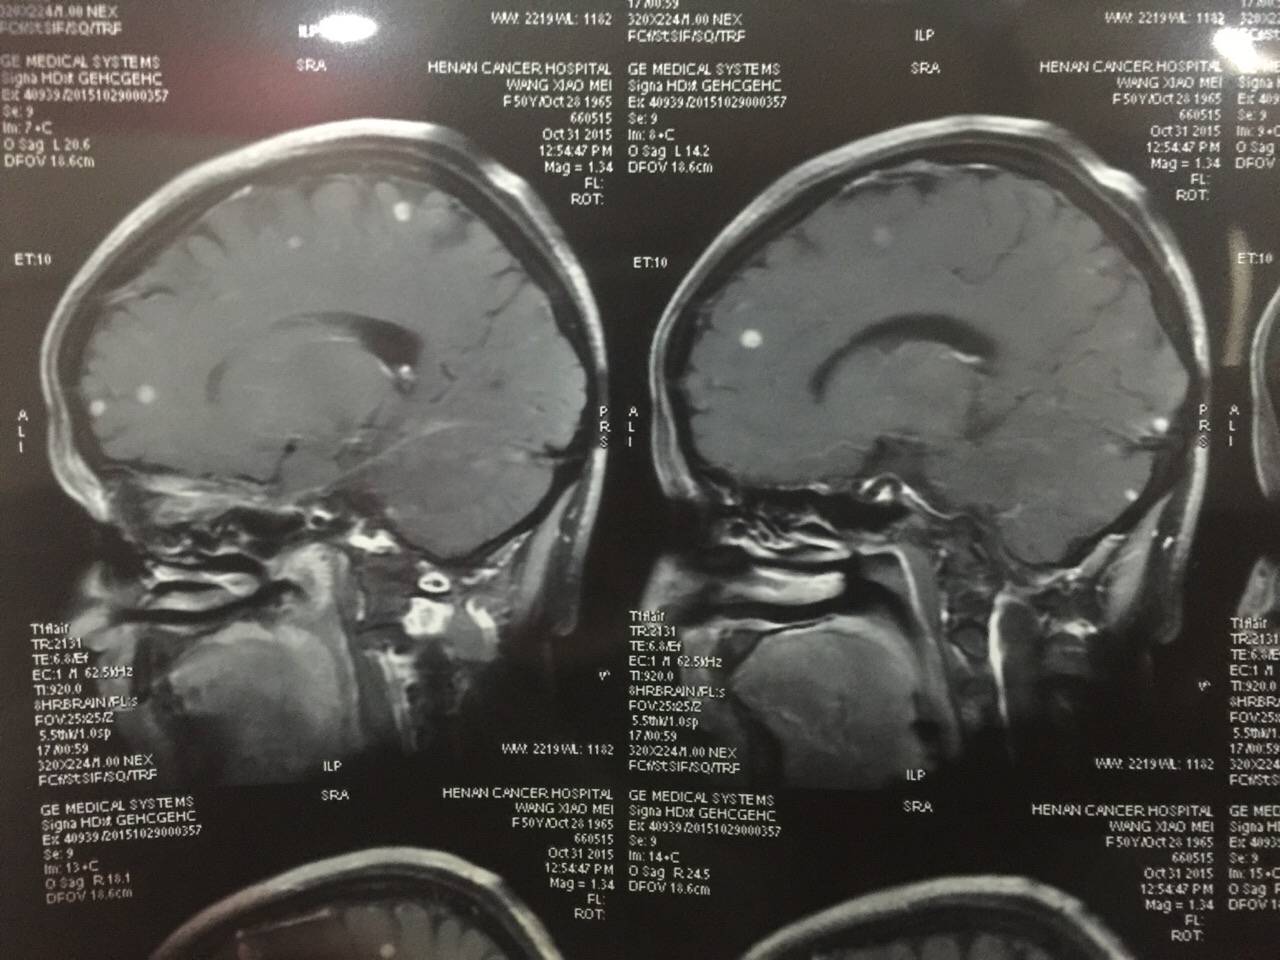

以下两张图是否是同一层面同一位置的图呢?

具体确定是看哪一个数值?

表示肿瘤的部位是不是亮光的圆点?

麻烦懂得高手指点一下,谢谢

每个图都是不同的层面 趁都还不是很大 赶紧处理

核磁隔层一般0.3或者0.5,每次躺的位置不同不可能完全扫到一个断层,但是医生会把有问题的选出来组成一套片子,如果这套新的片子转移灶明显变少,说明治疗有效。

目测不是完全同一层面